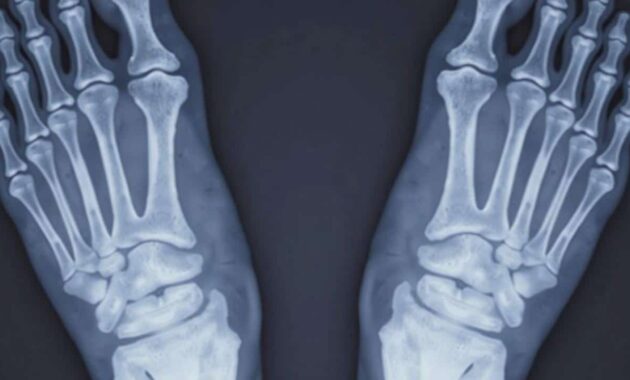

Foot and tendon issues like plantar fasciitis, Achilles tendinopathy and tennis elbow are often dismissed as simple inflammation that will fade with rest. For a proportion of patients, that story is wrong from the start.

Over months or years, repeated micro‑trauma can change the inner structure of the tendon or fascia. Collagen fibres lose their tidy alignment, tiny blood vessels invade where they shouldn’t, and the tissue’s capacity to heal itself drops. Pain becomes a daily companion, especially during the first steps in the morning or the first swings of a racket.